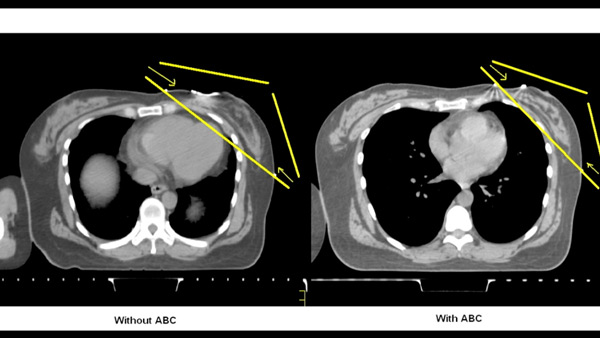

| A comparison of two heart images: without ABC (left) and with ABC (right). |